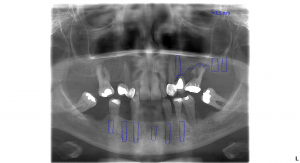

vrchná čeľusť: 3 zubné implantáty, sinus lift, 8 zirkónových koruniek, 1 endodoncia – ošetrenie koreňových kanálikov

spodná čeľusť: 6 zubných implantátov, 12 členný fixný keramický mostík

Najprv sa pacientka rozhodla pre ošetrenie spodnej čeľuste, kde bolo potrebných 6 zubných implantátov. Po implantácii bol pacientke nasadený dočasný, titánom vystužený mostík. Ten slúži ako dočasná zubná náhrada počas doby hojenia.